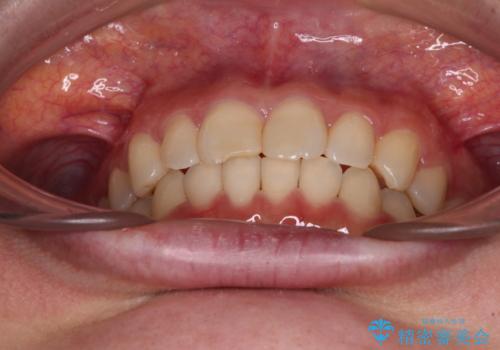

- 近々転勤の予定があるが、早めにインビザラインによる矯正治療を始めたいとのことで来院された患者様です。

上下ともにデコボコの程度は著しいものではなく、インビザラインで十分に対応可能な歯列不正でした。

後戻りによりスペースができてしまうことを避ける目的で、IPR(歯と歯の間を削る)を極力用いない矯正治療を行うこととしました。

インビザラインであれば来院間隔が多少長くなってもワイヤー矯正ほど問題とならないため、遠方からの通院であっても中断や転院せずに治療を行うことができます。